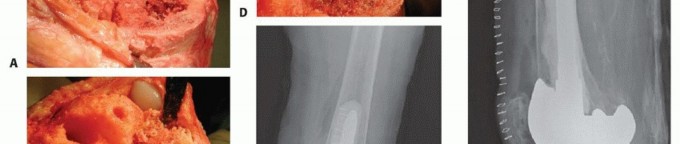

Component Extraction and Joint Debridement

Implant removal must be performed meticulously to preserve the remaining host bone stock. The interface between the implant and the bone or cement is disrupted using thin, flexible osteotomes, oscillating saws, and Gigli saws. Ultrasonic cement removal tools are highly advantageous for safely extracting cement mantles from the diaphyseal canal without causing iatrogenic cortical perforation or fracture.

Once the components are removed, a radical debridement of the joint is performed. All particulate debris, metallosis, and the inflammatory neocapsule must be excised. Osteolytic membranes lining the bone defects are thoroughly curetted until healthy, bleeding punctate bone is encountered. This debridement is critical, as residual osteolytic tissue can perpetuate the inflammatory cascade and compromise the incorporation of subsequent bone grafts.

Defect Classification and Preparation

Following debridement, the tibial bone defects are formally assessed and classified according to the Anderson Orthopaedic Research Institute criteria. The intramedullary canal of the tibia is sequentially reamed to determine the appropriate diameter and length of the diaphyseal stem required to bypass the metaphyseal defects and achieve stable cortical engagement in Zone 3.

The preparation of the defect depends on the planned reconstruction method. For contained defects, the sclerotic margins of the cavity are burred or drilled to expose a vascular bed capable of supporting graft incorporation. For uncontained defects slated for structural allografting, the host bone is typically prepared with a flat planar cut or a step cut to provide a stable, geometric seating surface for the allograft.